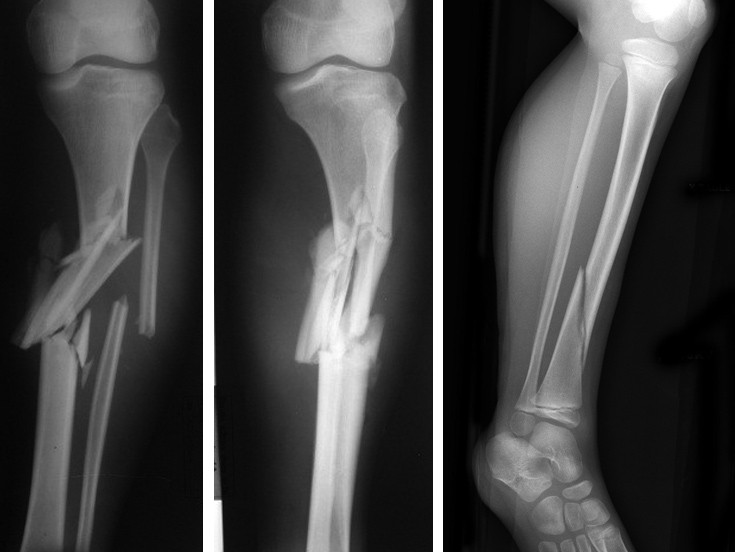

Τα κατάγματα της κνήμης είναι αρκετά συχνά γιατί το οστούν είναι εκτεθειμένο στις άμεσες κακώσεις επειδή στερείται μυϊκώς επαρκούς κάλυψης (κτυπήματα στο «καλάμι»). Συνήθως το κάταγμα της κνήμης συνοδεύεται από κάταγμα της περόνης, το οποίο όμως είναι άνευ σημασίας.

α) τα οφειλόμενα σε βαρεία κάκωση (π.χ. τροχαία) οπότε είναι και συντριπτικά και

Τα κατάγματα της κνήμης και ειδικότερα τα συντριπτικά έχουν χαρακτηριστική εμφάνιση. Το σκέλος έχει μεγάλη παραμόρφωση, μεγάλο οίδημα και παραφύσιν κίνηση (κουνιέται προς όλες τις κατευθύνσεις) προκαλείται οξύς πόνος!

Στο σπειροειδές κάταγμα αντίθετα, μοιάζει να είναι το σκέλος σταθερό, χωρίς παραμόρφωση του άξονα, απλώς φαίνεται στην περιοχή του κατάγματος η κνήμη διογκωμένη από το δηγιουργηθέν αιμάτωμα.

Τα κατάγματα αυτά (ανοικτά-επιπεπλεγμένα) συνήθως αντιμετωπίζονται με ακινητοποίηση με σύστημα εξωτερικής οστεοσύνθεσης. Τα κλειστά κατάγματα της κνήμης αντιμετωπίζονται με ενδομυελική ήλωση.

Τα σπειροειδή αντιθέτως κατάγματα, είναι καλοήθη. Επειδή έχουν μεγάλη επιφάνεια επαφής, πωρώνονται (κολλάνε) ταχέως. Συνήθως χρειάζεται μια βραχεία ακινητοποίηση σε νάρθηκα (3 εβδομάδες) και κατόπιν ένα νάρθηκα τύπου Sarmiento με τον οποίο ο αρχίζει ασθενής να βαδίζει φορτίζοντας μερικώς το σκέλος. Με τον τρόπο αυτό ευοδώνεται η πώρωση και το κάταγμα έχει κολλήσει μέσα σε 6 εβδομάδες.